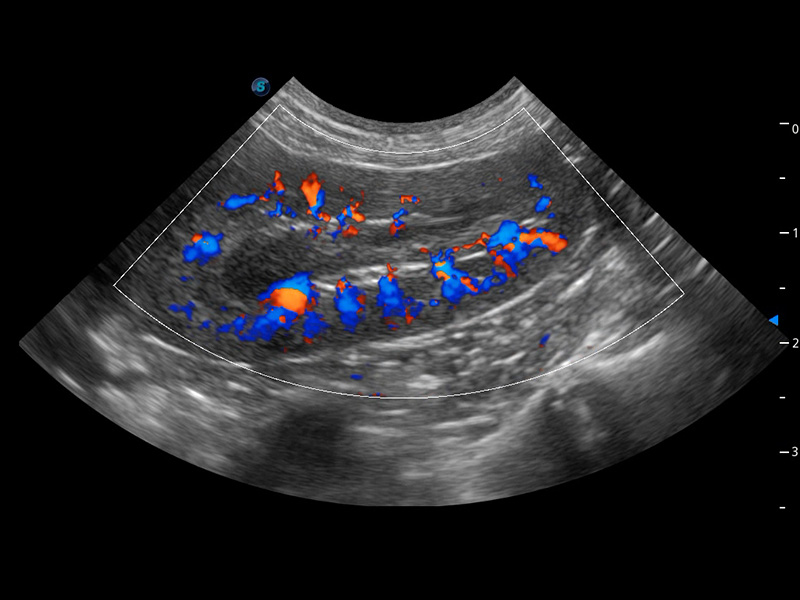

ProPet 60 作為一款高端臺(tái)式動(dòng)物超聲設(shè)備,為動(dòng)物醫(yī)生的日常診斷提供了一系列貼合動(dòng)物臨床需求、解決臨床實(shí)際問題的高級成像功能。憑借全系列高清探頭,滿足醫(yī)生對腹部、心臟、生殖、淺表、肌骨等成像的所有需求,切實(shí)幫助您提升檢查效率,提高診斷信心。